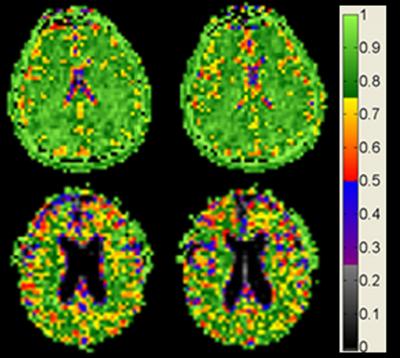

New, ultra-high-field magnetic resonance images (MRI) of the brain by researchers at the University of Illinois at Chicago provide the most detailed images to date to show that while the brain shrinks with age, brain cell density remains constant.

The images provide the first evidence that in normal aging, cell density is preserved throughout the brain, not just in specific regions, as previous studies on human brain tissue have shown. The findings also suggest that the maintenance of brain cell density may protect against cognitive impairment as the brain gradually shrinks in normal aging.

The images were made at UIC by a powerful 9.4-Tesla MRI, the first of its kind for human imaging. The 9.4 T magnetic field is more than three times stronger than that of a typical MRI machine in a doctor's office and is currently approved only for research. The strongest MRI units approved for clinical use are 3 T.

The 9.4 Tesla MRI measures sodium ions, which are less concentrated by several orders of magnitude than the fat and water molecules detected with standard MRI. Sodium ions are present throughout the body and are pumped in and out of neurons to generate the electric potentials needed to spark nerve impulses. Sodium concentrations in the brain reflect neuron density. Areas of low sodium concentration indicate lots of neurons packed tightly together, while higher sodium concentration can indicate more space between cells -- or the loss of cells, as in the case of neurodegenerative diseases.